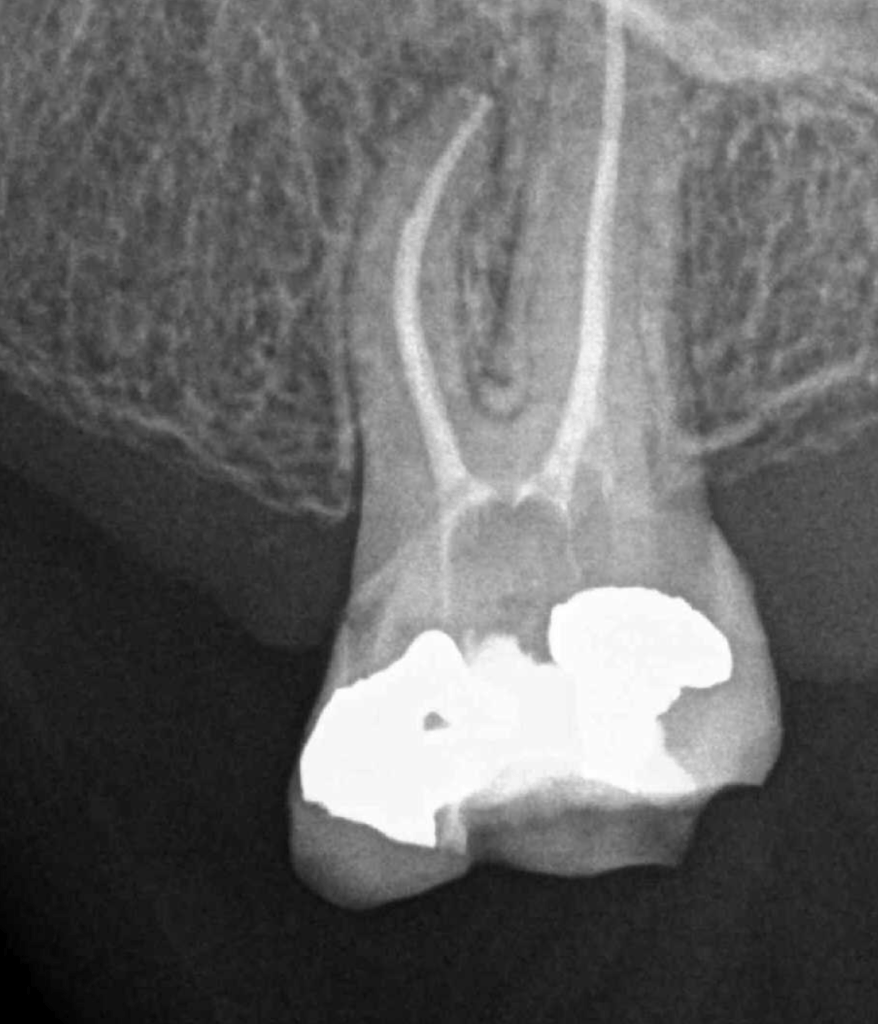

Fisura, remoción amalgama para explorar